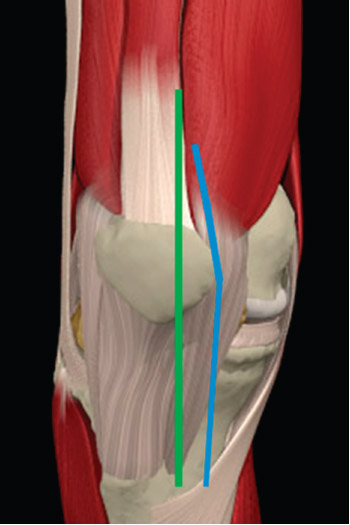

In May 2006, the senior author (W.M.G.) modified his traditional midline total knee arthroplasty incision by moving it medially to avoid pressure areas identified during the kneeling process. By the end of 2006, this surgeon had performed this incision during the treatment of 281 consecutive knees in non-obese patients. The incision started 2 to 3 cm medial to the tip of the tibial tubercle, lined up just medial to the medial edge of the patella. At the top of the patella, the incision was gradually angled laterally toward the quadriceps tendon. The incision was lengthened along the midline if excessive tension was observed in the skin. The capsular incision was made along this same path. At the top of the patella, a 5- mm cuff of quadriceps tendon was created and the incision was extended 1 to 2 cm and then into the vastus medialis. The patella was everted, and the knee was flexed (Fig. 6).

fig 6

Fig. 6 Illustration depicting the traditional midline total knee arthroplasty incision (left, green) and new medial midline incision (right, blue). (Reprinted, with permission, from Primal Pictures Ltd., London, United Kingdom.)